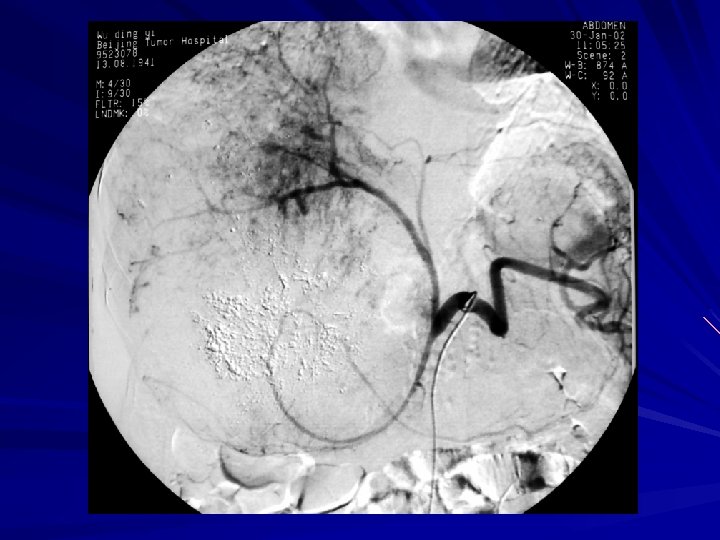

Use of microcatheter—TACE

Use of micro-catheter—first TACE

Use of micro-catheter— 2 nd TACE -----OA branches involved in blood supply-----

Use of microcatheter— OAs TACE

Use of microcatheter —KUB after OAs TACE